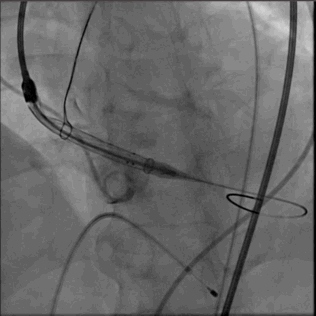

5.完全释放瓣膜

6.猪尾导管拉回 放置新的人工瓣膜工作区域上方造影

7.瓣膜支架未完全打开,返流 PVL均存在,决定后扩

8.支架展开形态良好 返流大幅度减少

9.仅在钙化严重,窦交界区域有PVL,符合术前预估